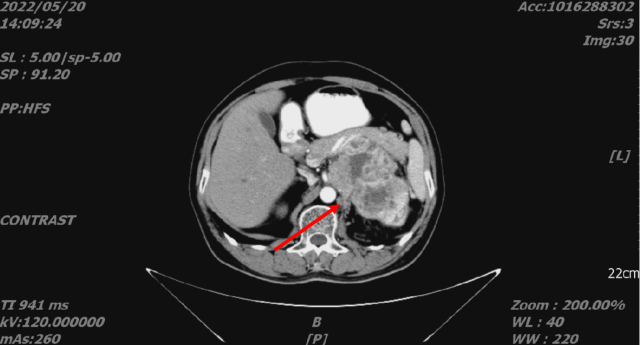

2022-05-20 CT:

舒尼替尼治疗后,2022-08-15 复查 CT

1. 结合临床,左肾癌治疗后,较前片 2022-5-20 好转;左侧肾上腺受累;考虑肝转移,较前缩小或显示不清。

2. 双肺转移,较前好转。

3. 前列腺钙化灶。

4. L5 双侧椎弓崩解;L2 椎体致密灶,建议观察。